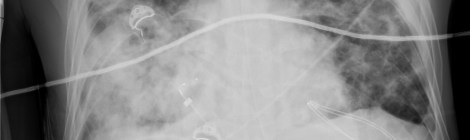

The flu, this year, is Bad.  I have had my first patient die from it. It’s not just suffocation from respiratory failure, as the lungs fill with fluid such as […]